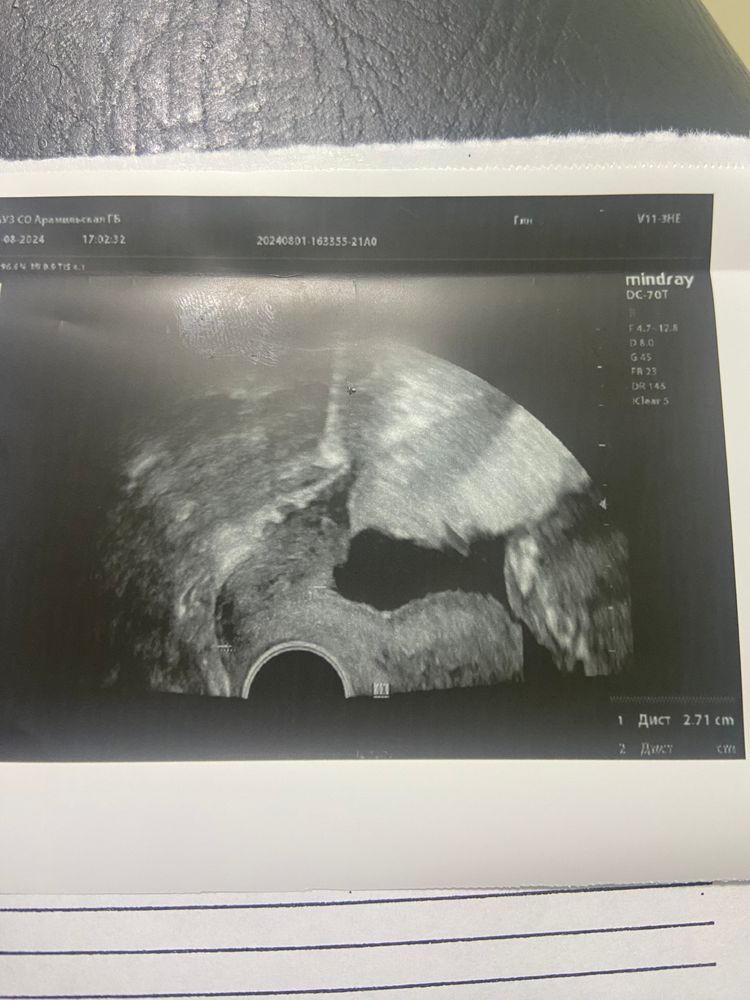

Насколько расширен, это важно… судя по картинке узи у вас хороший такой тонус был на момент осмотра… я, честно, не вижу расширения зева. Но это картинка… надо смотреть в динамике. Анамнез у вас не отягощен по ИЦН?

ЛанаРей, дак вот и я сижу с этим узи и не могу понять… толком ни чего не написано, на сколько расширен что и как….

Кристина, я бы повторила цервикометрию дней через 5-7. Только в адекватном месте)